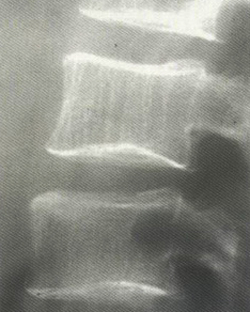

Для определения плотности костей используют однофотонную (не всегда информативна) и двухфотонную денситометрию, ультразвуковую денситометрию и количественную КТ позвоночника. Рентгенологические методы исследования позволяют достоверно выявить признаки остеопороза только при значительной потере массы костных тканей (более 30%).

остеопороз вторичной степени, или умеренный — очевидное снижение плотности костной ткани. При этом тела позвонков обретают специфическую двояковогнутую форму, формируется деформация клиновидной формы одного из позвонков. Эта степень недуга проявляется в сильнейших болезненных ощущениях;

выраженный остеопороз, или третичная степень — происходит выявление резкой прозрачности позвонков при рентгенологическом обследовании. Иначе это называется остекленением и присутствием деформации клиновидного типа единовременно в нескольких позвонках. На данной стадии остеопороз уже очевиден.

Разработано достаточное количество способов, при помощи которых осуществляется диагностика остеопороза. Рентгенография даёт возможность обнаружить истощение костных тканей лишь тогда, когда их потери достигли более чем 30%. Поэтому к данному методу имеет смысл прибегать исключительно при вторичной степени недуга.

Более современным методов, который практически всегда осуществляется при остеопорозе, является анализ высоты отделов позвоночника и подсчет их взаимоотношения. Оптимальным способом следует считать денситометрию. Именно это даёт возможность максимально точно обозначить степень плотности костных тканей, соотношение кальция в организме человека, а также число мышечных и жировых отложений.